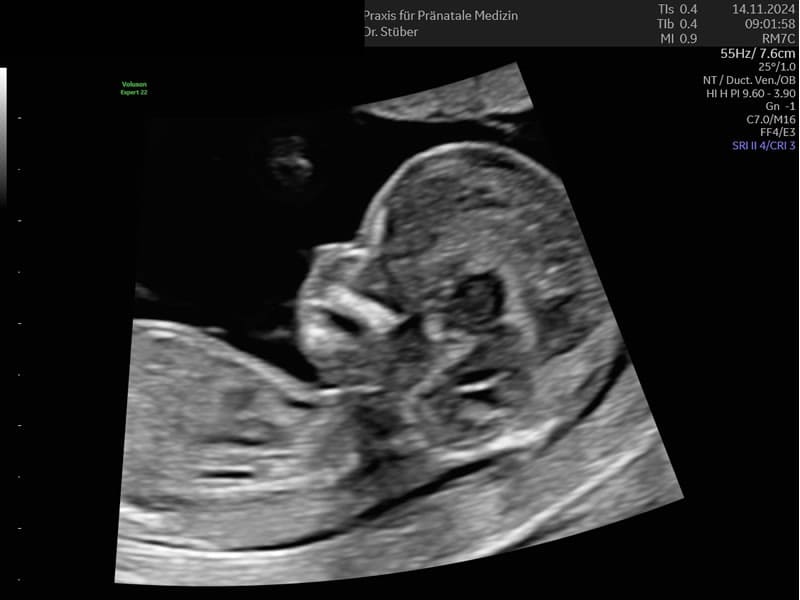

Im ersten Trimenon (1. Schwangerschaftsdrittel) bieten wir Ihnen verschiedene Untersuchungen an. Ab der 12. SSW können unter anderem bereits Kopf, Herz und Extremitäten untersucht und einige Fehlbildungen ausgeschlossen werden.

Im Ersttrimesterscreening (12-14 SSW) können wir durch Messen der Nackentransparenz, Darstellung des Nasenbeins und weitere Parameter zusätzlich das Risiko für Chromosomenstörungen bei Ihrem Kind ermitteln.